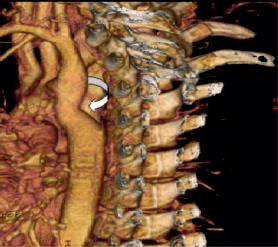

For multiple-sided visualization of the stenosis, the patient underwent evaluation by MDCT.

Figure 9. Pre-stenting MDCT of Pacient A. 3D VR (Volume Rendering) Mode. The level of aortic coarctation is determined; coronary sinus and aortic arch.

Figure 8. Pre-stenting MDCT of pacient A. Sagittal projection of the aortic arch and descending Ao. The white arrow – descending thoracic Ao stenosis. The yellow arrow – the aorta arch. The blue arrow – Left subclavian artery.